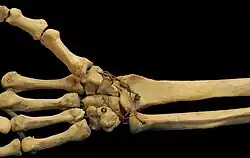

The carpal bones, sometimes included in the definition of the wrist